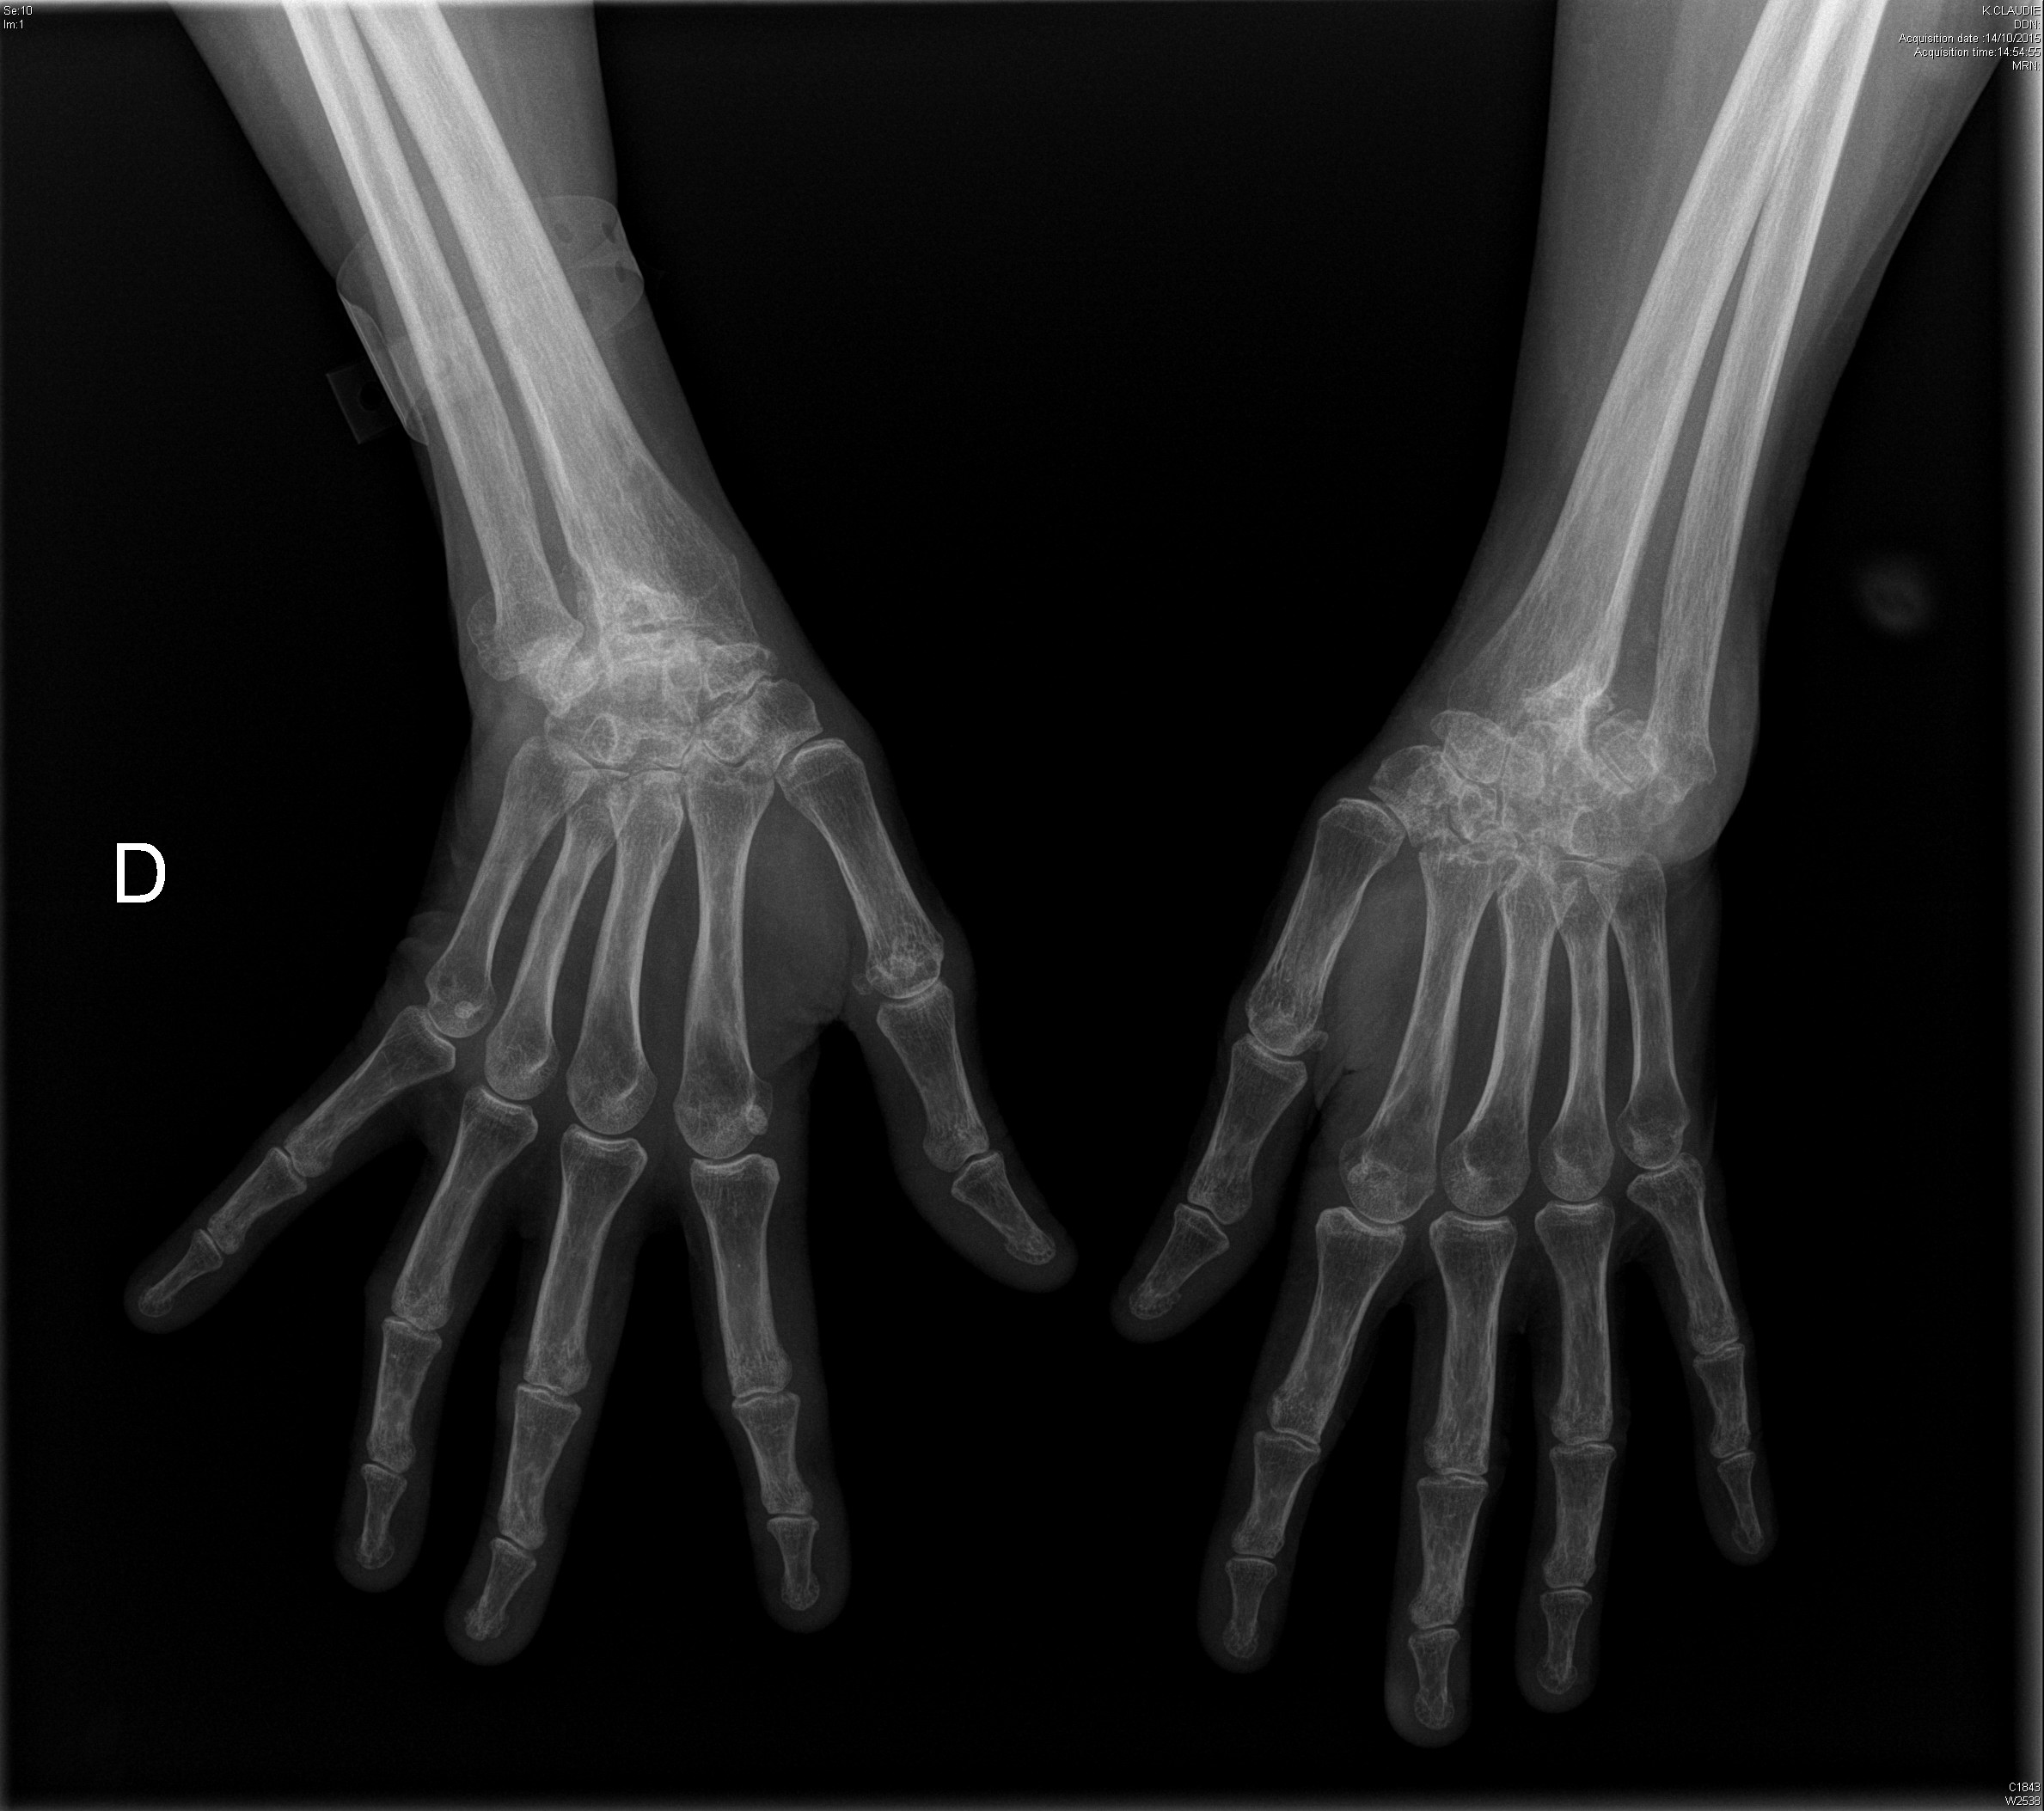

Carpite bilatérale évoluée dans le cadre d'une polyarthrite rhumatoïde